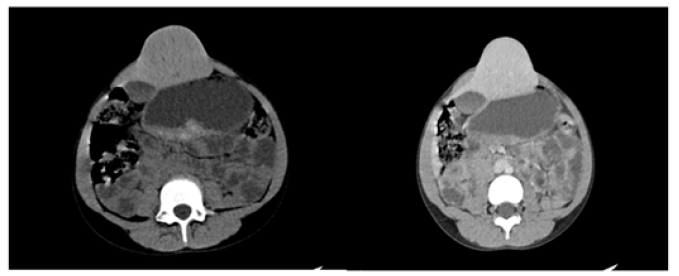

An abdominal CT scan showed huge epigastric hernia containing the left liver lobe (Figure 1a, 1b and 2a, 2b). A supra-umbilical laparotomy was performed for ventral hernia repair. An important hernia sac was dissected and opened revealing epiploic appendages and liver as content. The exploration found liver segment II & III as the majority contents. Hernia mesh repair was performed, and mesh placed in the retro muscular position.

In our case, the portal vein and hepatic arteries appeared normal on CT scan with no obvious vascular compromise to the liver parenchyma. Segment II and III of liver showed no hypodensity indicating ischemia on Triple Phase CT scan with no evidence of an inflammatory reaction in or around the liver parenchyma. The blood picture revealed no evidence of inflammation with normal ESR , normal WBC, and no abnormal liver function test.